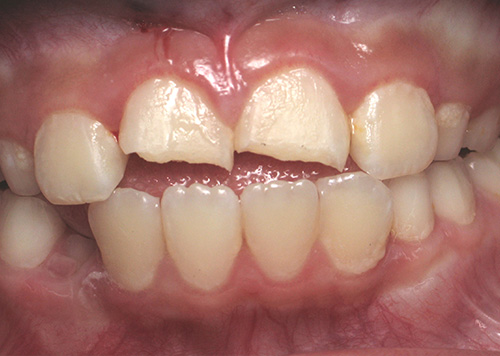

Smile Gallery

Orthodontic Treatment X-ray - Before

After Series of Teeth Extractions, Upper Left Canine Unerupted.